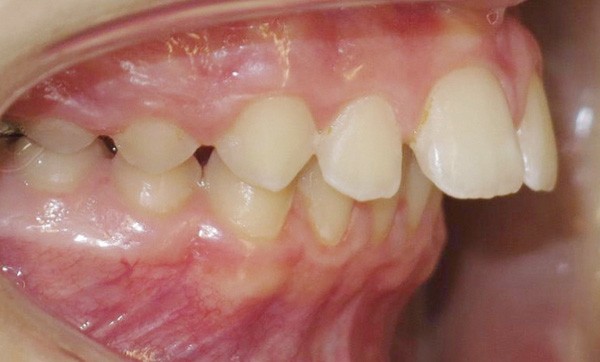

Mlle B. présente une classe II squelettique par retrognathie mandibulaire dans un contexte vertical hypodivergent. La patiente a déjà bénéficié de deux semestres interceptifs avec le port d’une force extra-orale. Le visage est symétrique, le sourire est timide et découvre peu les dents. L’angle naso-labial est ouvert, l’interposition labiale inférieure constante et la distance cervico-mentonnière réduite (fig. 1 à 3).

Le parodonte est fin et festonné mais l’hygiène est maîtrisée. On retrouve une endoalvéolie maxillaire relative à la classe II, une supraclusion incisive d’origine mandibulaire, une biproalvéolie incisive, un surplomb incisif de 9 mm associé à une classe II dentaire sévère (fig. 3 à 6).